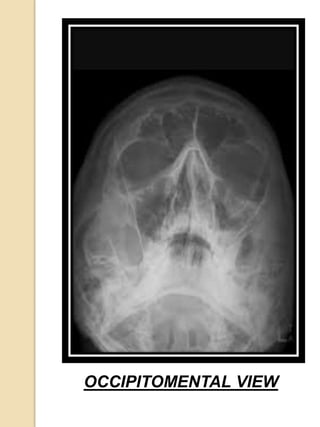

RADIOGRAPHIC

EVALUATION

 Lateral views of the nasal

bones,15° or 30°

occipitomental projections

can be taken.

 A lateral view taken with

small dental film against the

side of the nose also

provides excellent detailed

study.

 CT scan is helpful for higher

level fractures of the nose.

OCCIPITOMENTAL VIEW